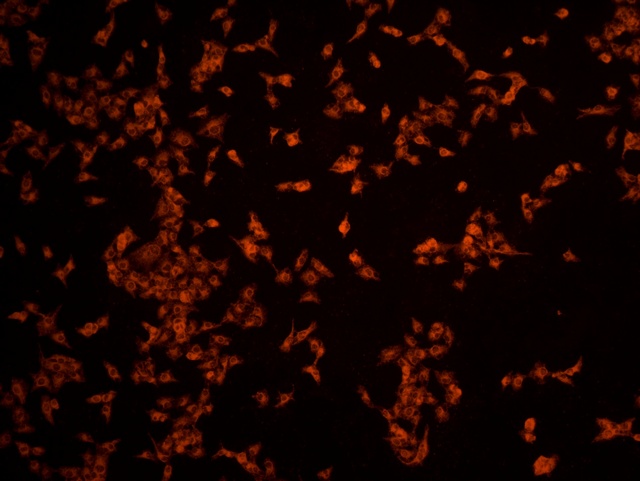

南華大學(xué)在生物醫(yī)學(xué)研究領(lǐng)域一直走在學(xué)術(shù)前沿,近日,該校引進(jìn)Mshot明美的倒置熒光顯微鏡MF52-N,搭配顯微鏡相機(jī)MSX2,為細(xì)胞切片標(biāo)本的研究提供了強(qiáng)大的技術(shù)支持,進(jìn)一步提升了科研實(shí)力。

MF52-N倒置熒光顯微鏡以其數(shù)顯LED熒光模塊和深度優(yōu)化的光路設(shè)計(jì),成為細(xì)胞切片觀察的理想選擇。其簡(jiǎn)單易用的熒光激發(fā)操作,大大降低了實(shí)驗(yàn)難度,提升了工作效率。同時(shí),該顯微鏡還能提供高質(zhì)量的相襯、熒光和明場(chǎng)成像,確??蒲腥藛T能夠捕捉到細(xì)胞切片的每一個(gè)細(xì)節(jié)。

在南華大學(xué)的實(shí)驗(yàn)室中,科研人員正借助這套先進(jìn)的顯微系統(tǒng),對(duì)細(xì)胞切片標(biāo)本進(jìn)行深入探索。

此外,MSX2顯微鏡相機(jī)的加入,更是如虎添翼。這款相機(jī)以其高分辨率和敏銳的圖像捕捉能力,記錄了實(shí)驗(yàn)過程中的每一個(gè)重要瞬間,為數(shù)據(jù)分析與論文發(fā)表提供了有力支持。